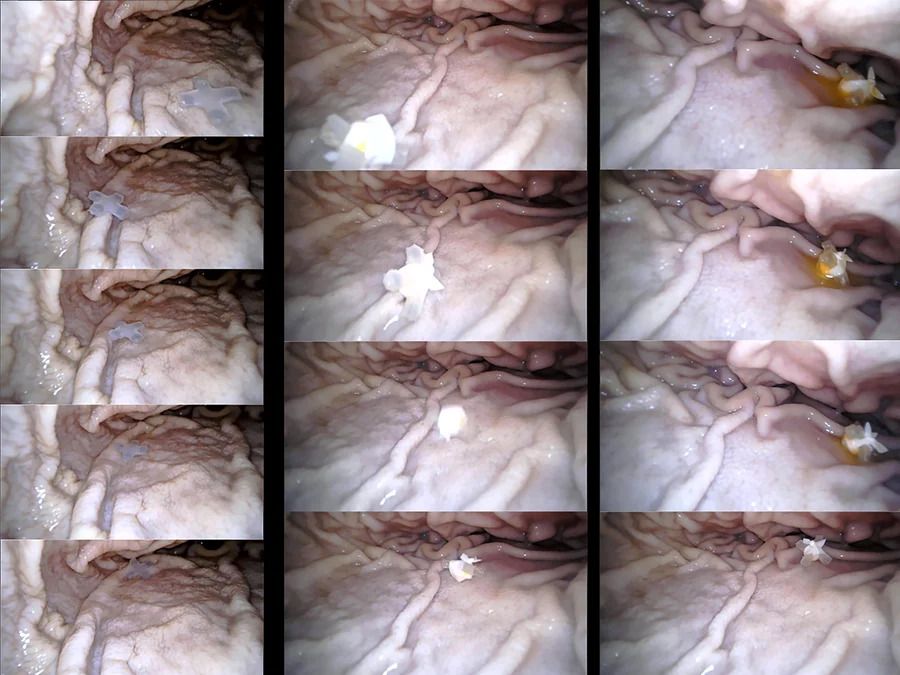

A mintájára fejlesztett, gumiszerű, mágneses anyagból készült robotot eddig állatok gyomrában, vastagbelében és vékonybelében tesztelték. Sikeresen eligazodott az emésztőrendszer bonyolult rendszerében, ami pedig tele van nyálkával, éles kanyarokkal és akár 8 centiméter magas akadályokkal.